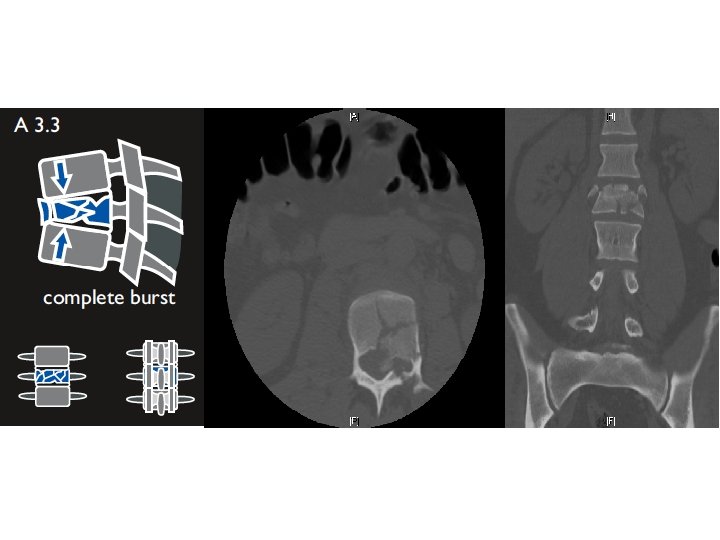

22 M motorcycle crash Motor - 2/5 hip flexion and knee extension - 0/5 below knee - diminished rectal tone Sensory - Diminished sensation to light touch below knee Reflexes - None at knees and patella - No clonus 3 rd degree instability TLICS 9 (3+3+3) ASIA C

1 st attempt at surgery: Aborted due to sacral hemorrhage Wound packed Pelvic binder placed Sacral vessels embolized Transfused p. RBC, FFP, plts Returned to OR 2 days later…

Post op result L 1 -L 5 segmental instrumentation and posterolateral fusion Correction of fracture-dislocation using Wilson frame and reduction screws Motor - unchanged Sensory - some ROF below knees Bracing - TLSO Follow up - 6 week repeat X rays Not yet